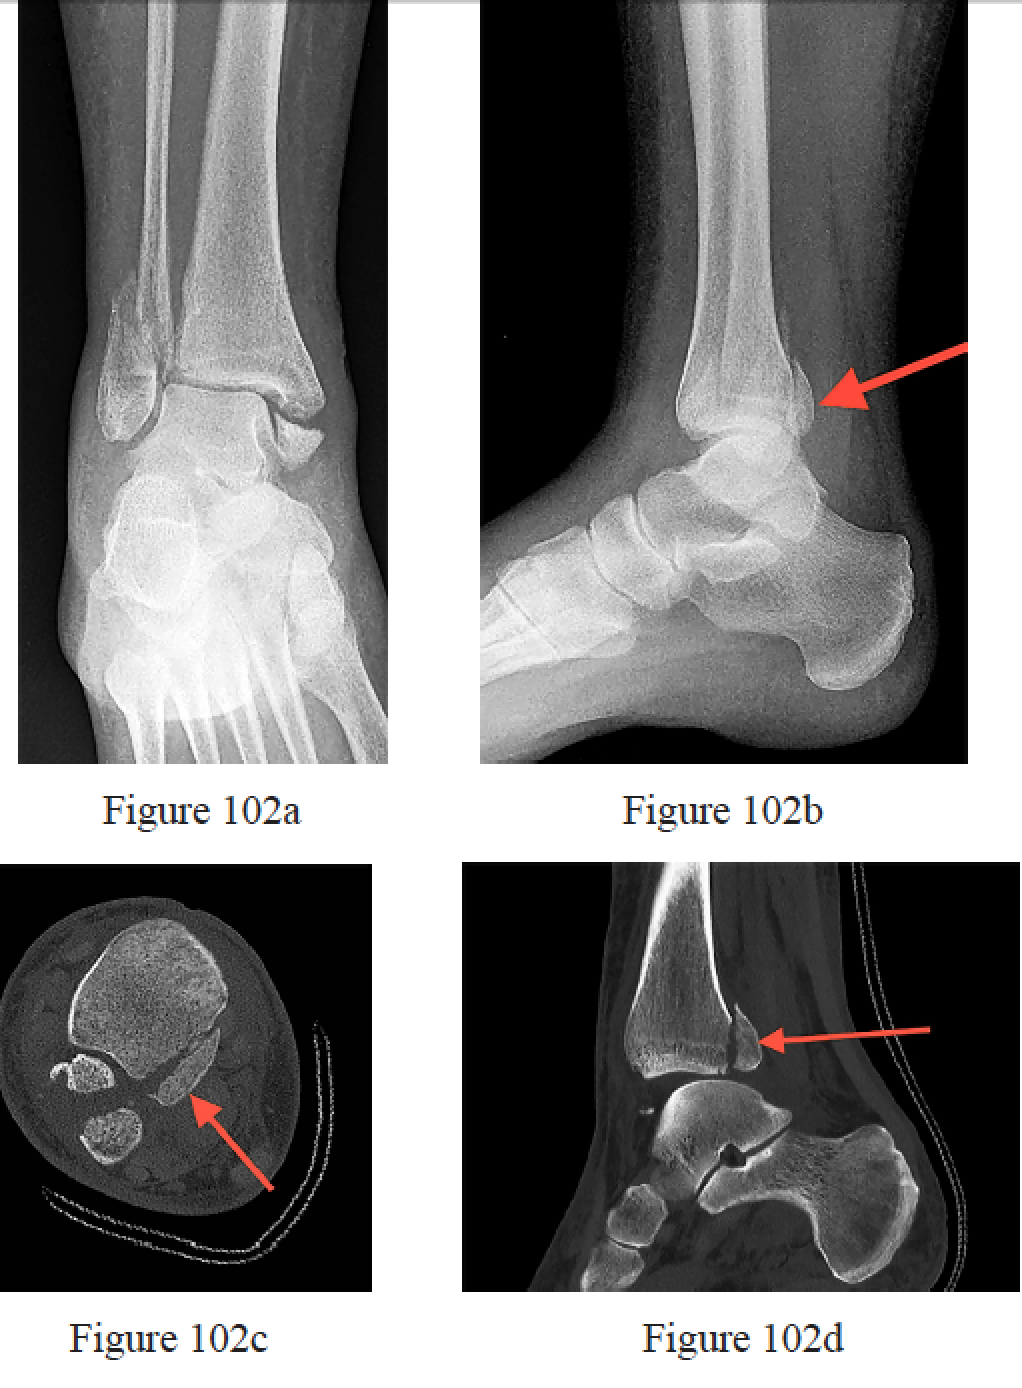

Irwin TA, Lien J, Kadakia AR. Posterior malleolus fracture. J Am Acad Orthop Surg. 2013 Jan;21(1):32- 40. doi: 10.5435/JAAOS-21-01-32. Review. PubMed PMID: 23281469.

Tornetta P 3rd, Ostrum RF, Trafton PG. Trimalleolar ankle fracture. J Orthop Trauma. 2001 Nov;15(8):588-90. PubMed PMID: 11733680.